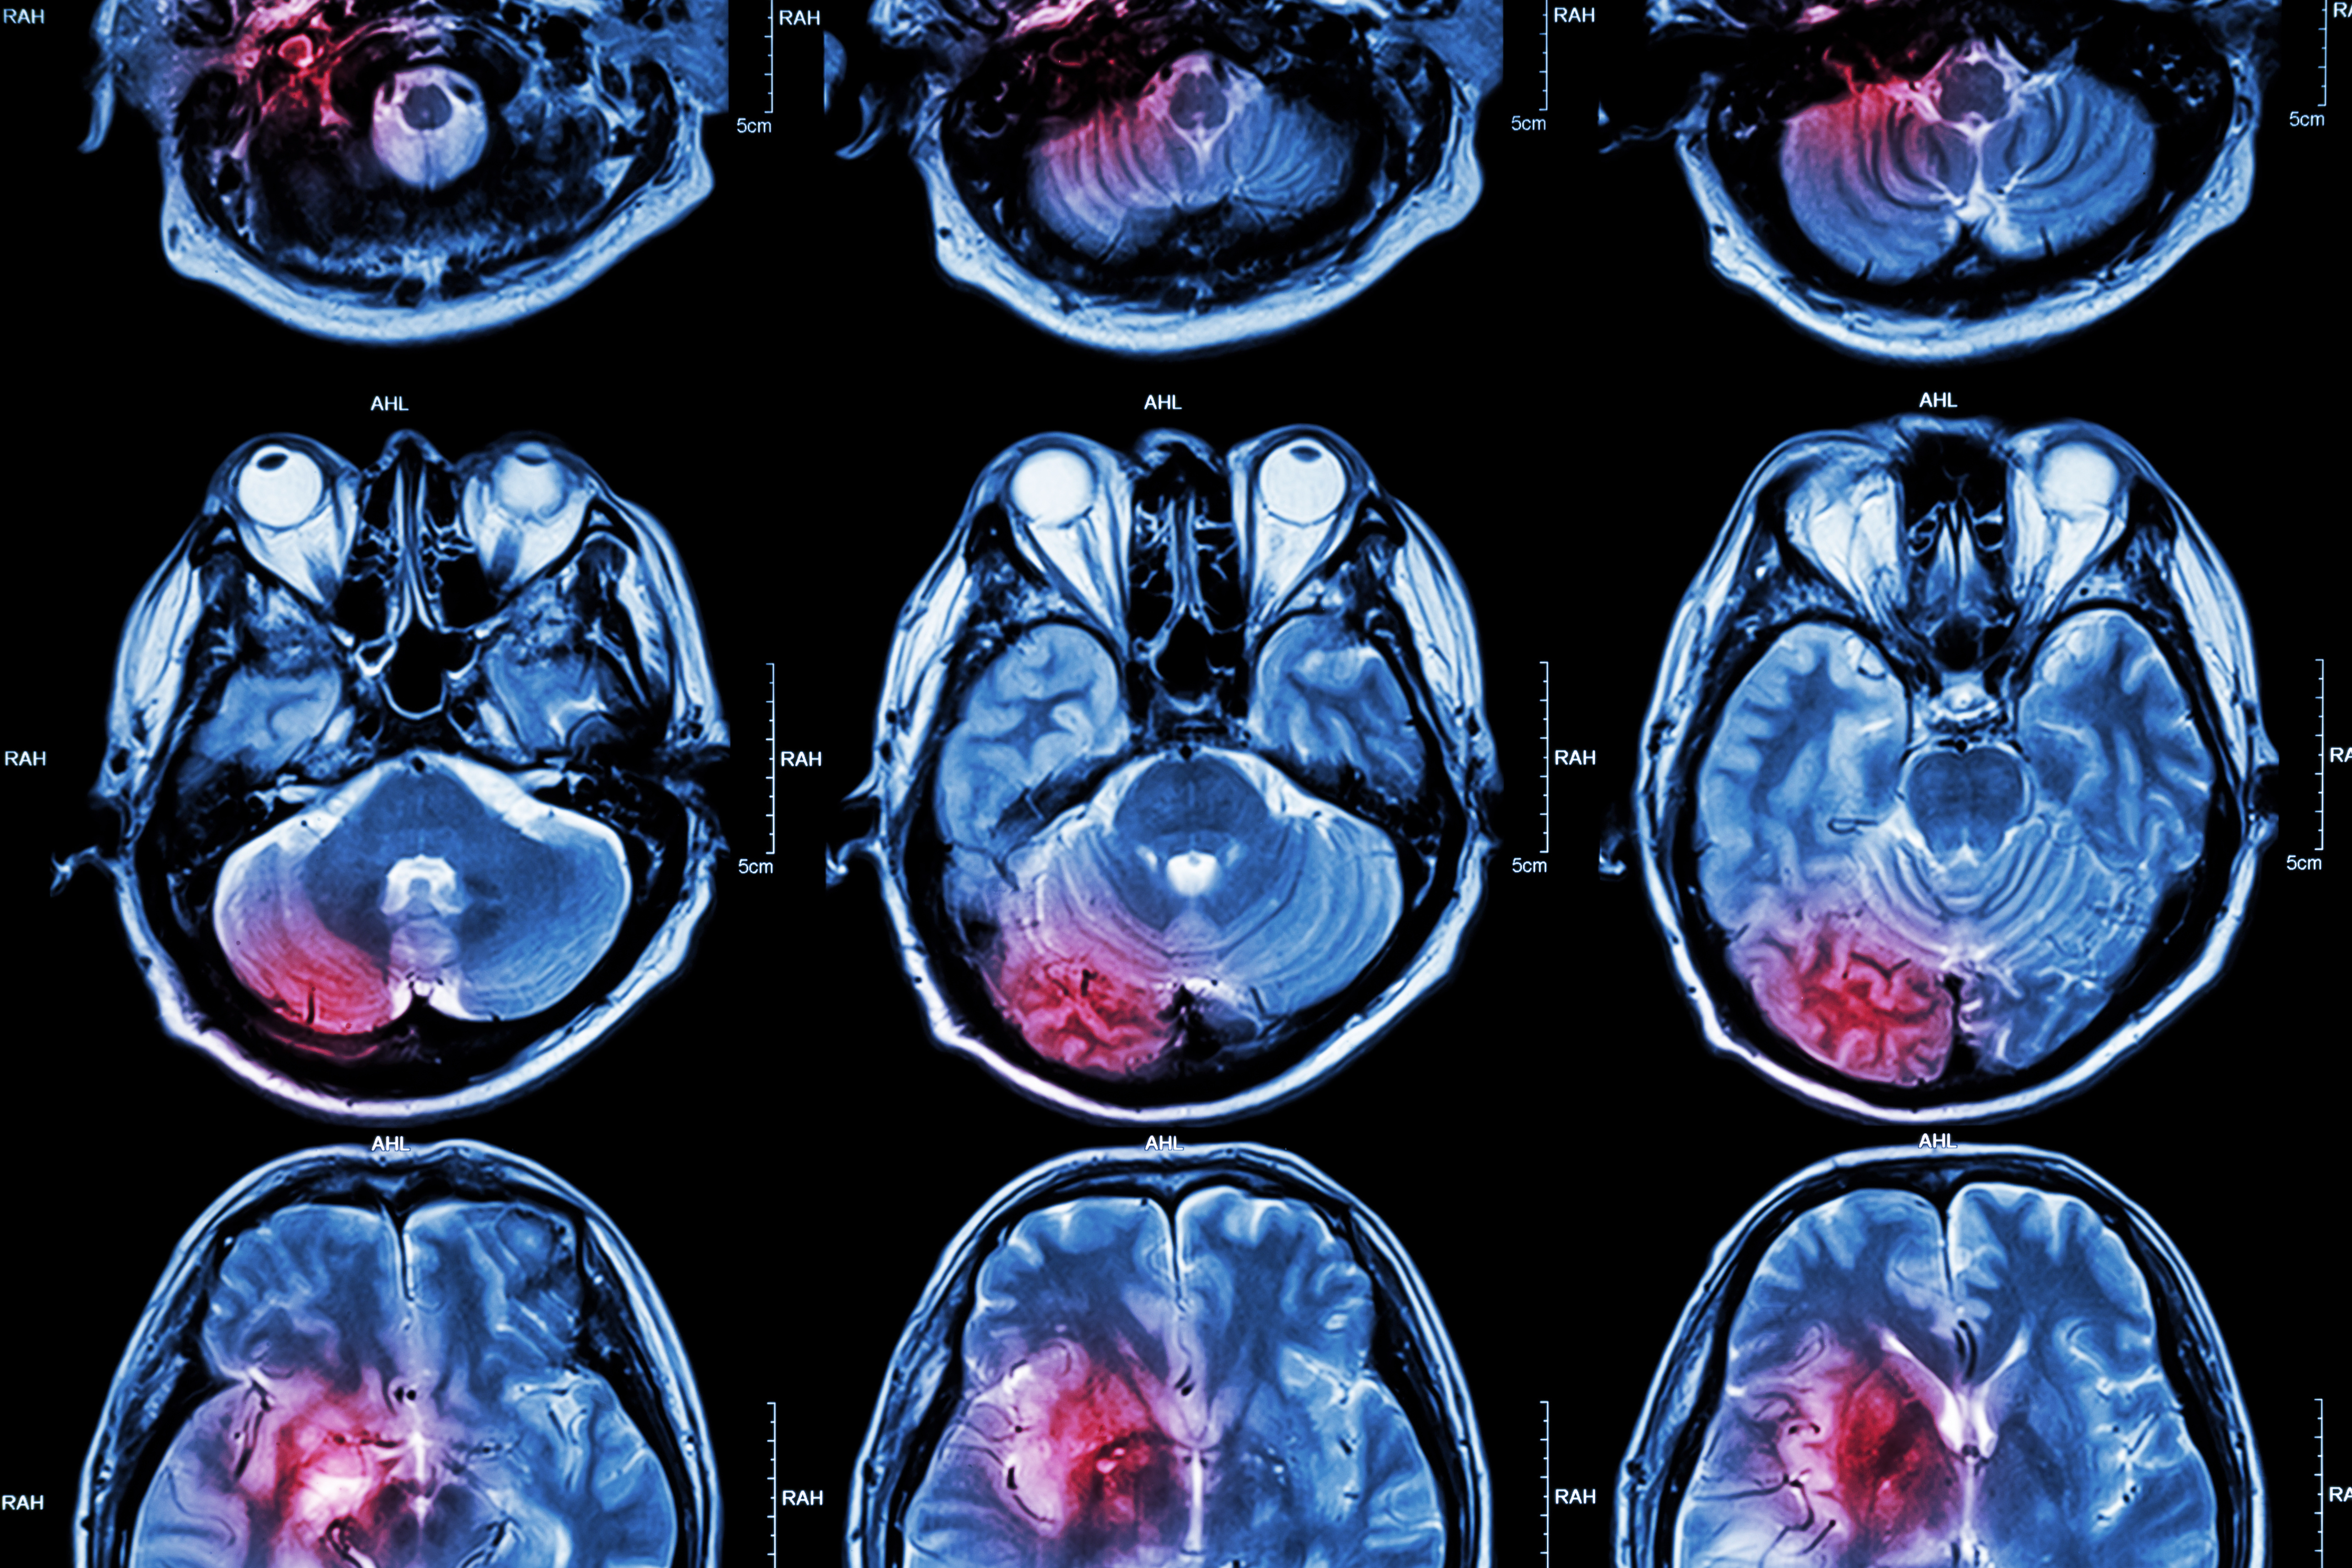

Wellumio, a New Zealand-based medical device company specializing in stroke detection, has enrolled the first patient in a feasibility, safety, and usability assessment of its Axana 0.1-tesla portable MRI device.

A Melbourne, Australia-based hospital recently used Axana to perform an exam on a 77-year-old woman suspected of acute stroke.

Axana's technology is powered by pulsed gradient-free mapping (PGFM), which eliminates the need for bulky components and allows for the imaging of biomarkers through a portable design ideal for bedside use, the company said.